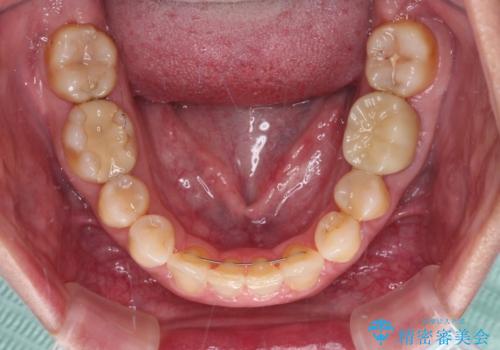

マウスピースでの抜歯矯正特有の抜歯スペースに向かって奥歯が傾斜する動きが顕著に表れ、ディープバイトは改善されませんでした。

前歯のみが強く接触し、奥歯で咬めない期間も続いたため、ワイヤー装置などを補助的に使用し、何とか終了させることができました。